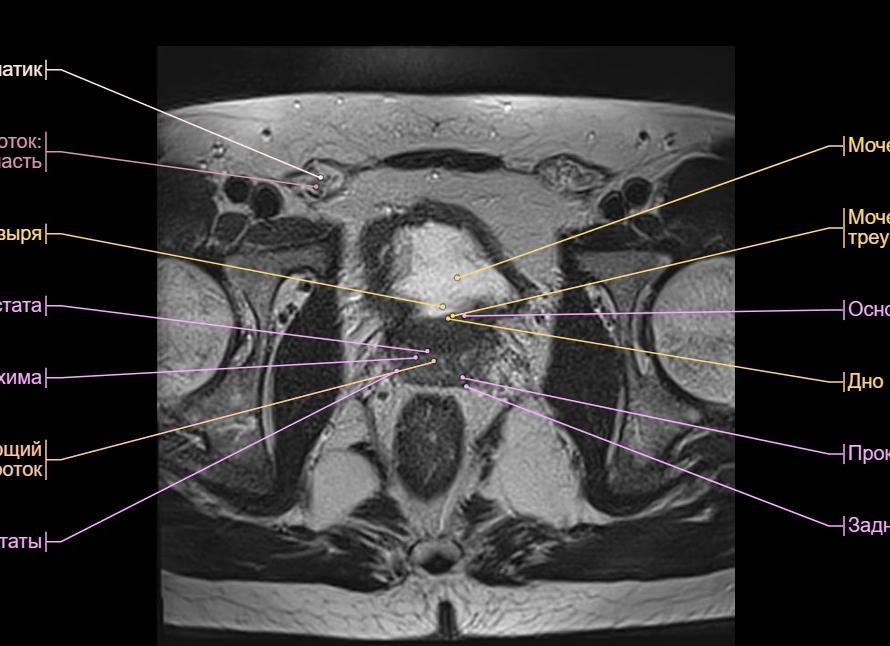

МРТ органов малого таза у женщин и мужчин назначается с целью визуализации следующих внутренних органов:

- У женщин: влагалище, матка и придатки.

- У мужчин: простата, протоки, наружные половые органы.

- Мочеиспускательный канал, мочевой пузырь, лимфатическая и сосудистая система.